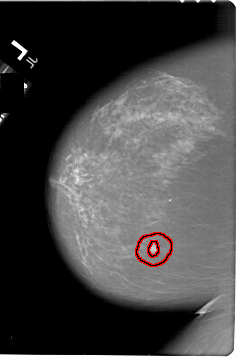

A_1821_1.LEFT_MLO

LEFT_MLO LINES 6781 PIXELS_PER_LINE 4576 BITS_PER_PIXEL 12 RESOLUTION 43.5 OVERLAY

FILE: A_1821_1.LEFT_MLO.OVERLAY

TOTAL_ABNORMALITIES 1

ABNORMALITY 1

LESION_TYPE MASS SHAPE IRREGULAR MARGINS SPICULATED

ASSESSMENT 5

SUBTLETY 5

PATHOLOGY MALIGNANT

TOTAL_OUTLINES 1

BOUNDARY